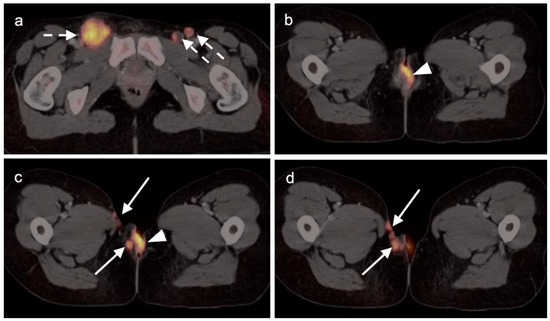

3.1. Prostate Cancer